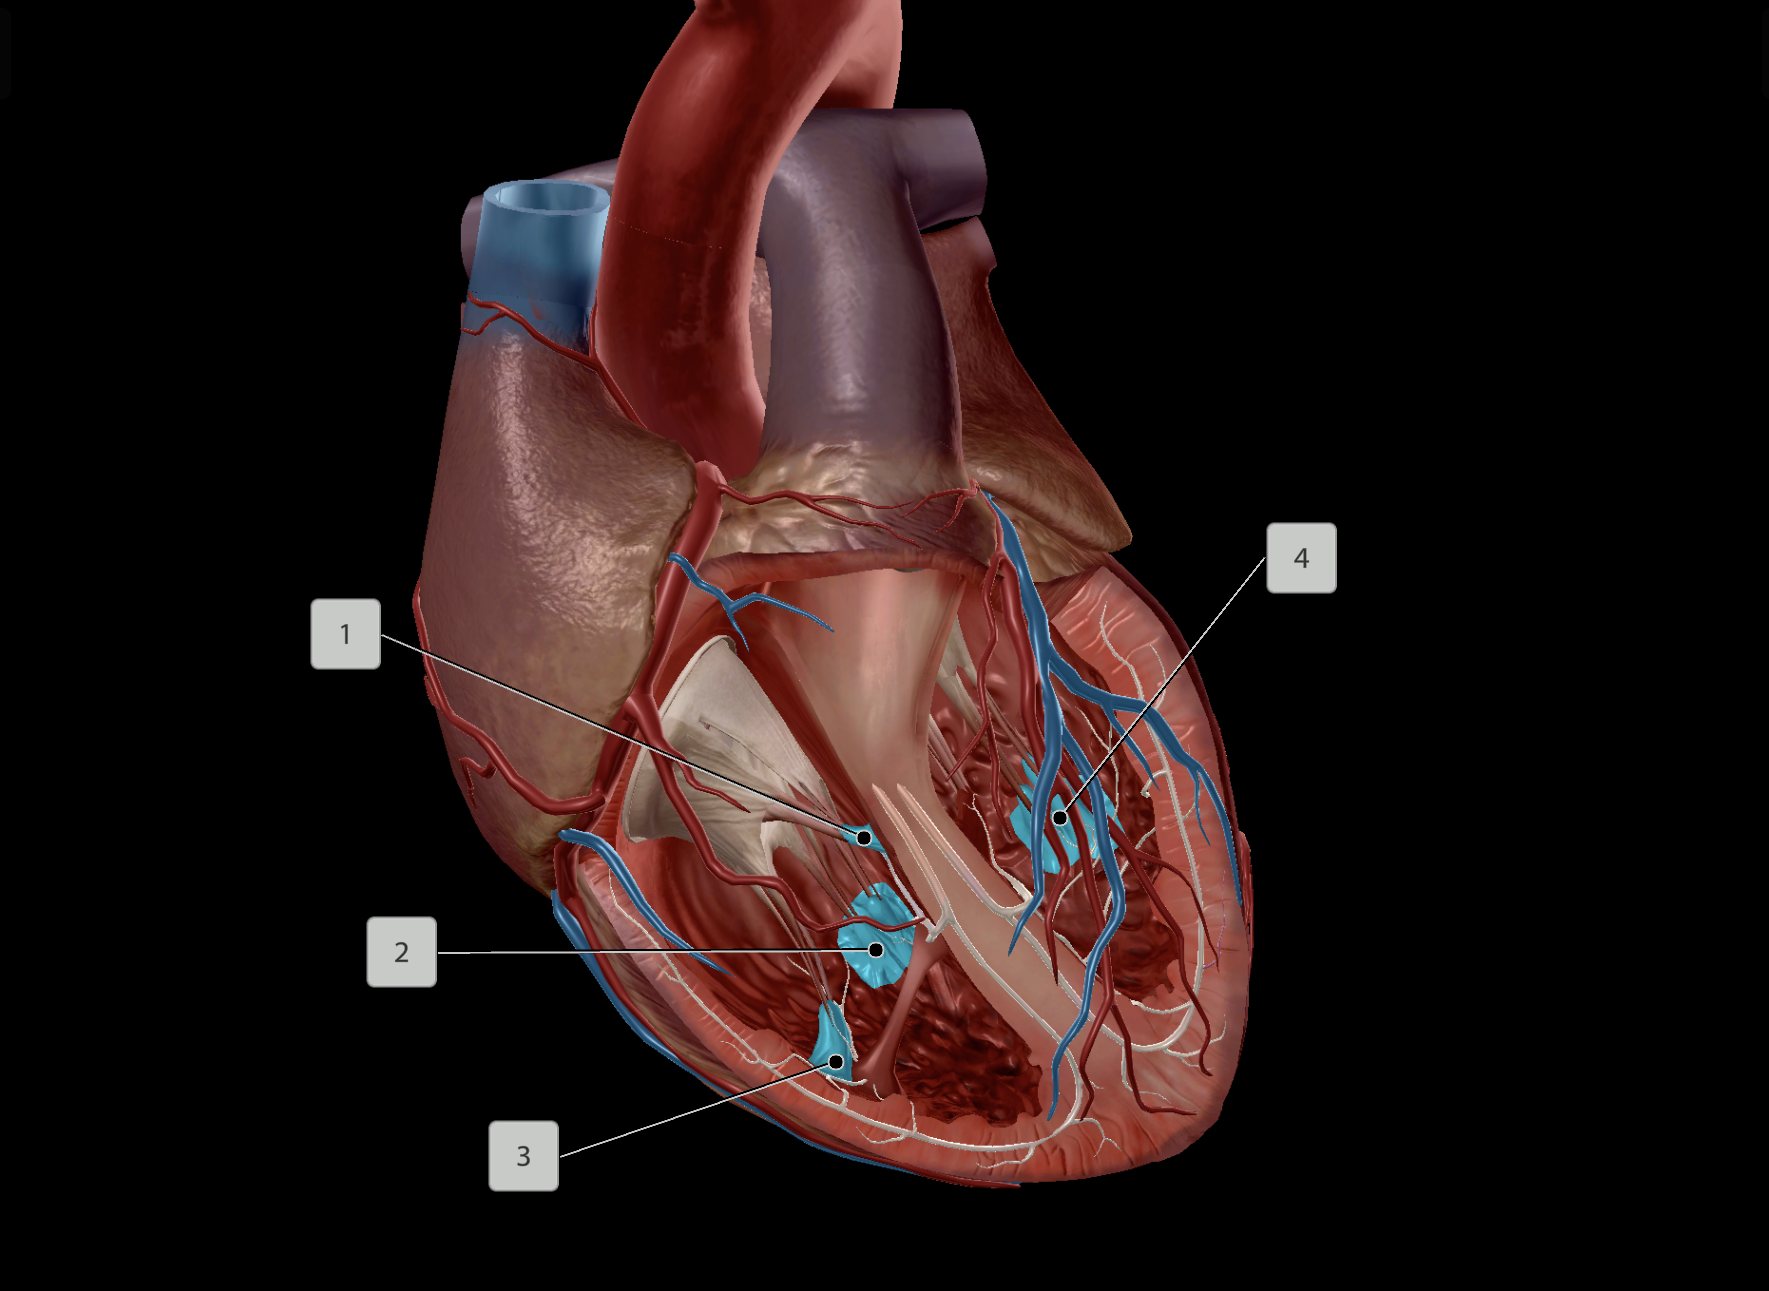

Tricuspid Valve

Bicuspid Valve

Aortic Valve

Papillary Muscle

Pulmonary Valve

Interventricular Septum

Chordae Tendineae

Anterior Interventricular Artery

Circumflex Branch

Coronary Artery

Middle Cardiac Vein

AV Node

SA Node

Bundle of His

Coronary Sinus

Anterior Interventricular Sulcus

Interatrial Septum

Coronary Sulcus

Small Cardiac Vein

Anterior Cardiac Vein

Posterior Interventricular Sulcus/Artery

Coronary Veins

Marginal Branch

Circumflex Artery

Great Cardiac Vein